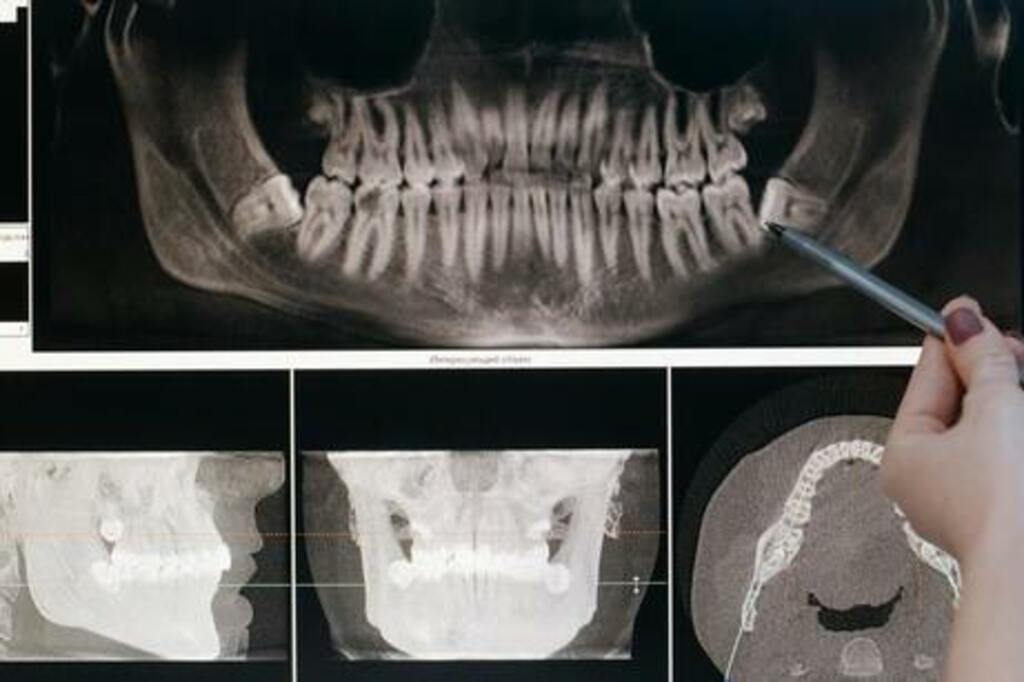

Wisdom teeth, also known as third molars, usually erupt in the late teens or early twenties. While some people may not face issues with their wisdom teeth, many experience discomfort, pain, or complications like impaction. In such cases, wisdom tooth extraction is the best solution to maintain oral health and prevent future problems. At our dental clinic in Bhubaneswar, we offer safe and painless wisdom tooth extraction services to ensure a smooth recovery and optimal dental health.

These teeth can become trapped under the gums or grow at an angle, causing discomfort or infection.

Wisdom teeth can be difficult to clean, leading to decay and infection.

Wisdom teeth are prone to infections that can spread to nearby teeth or the jawbone.

Removing impacted or misaligned wisdom teeth can reduce jaw pain, headaches, and swelling.

Removing problematic wisdom teeth can prevent future dental issues like tooth decay, gum disease, and shifting of teeth.

At our Bhubaneswar clinic, we follow a comprehensive and patient-focused approach for wisdom tooth extraction